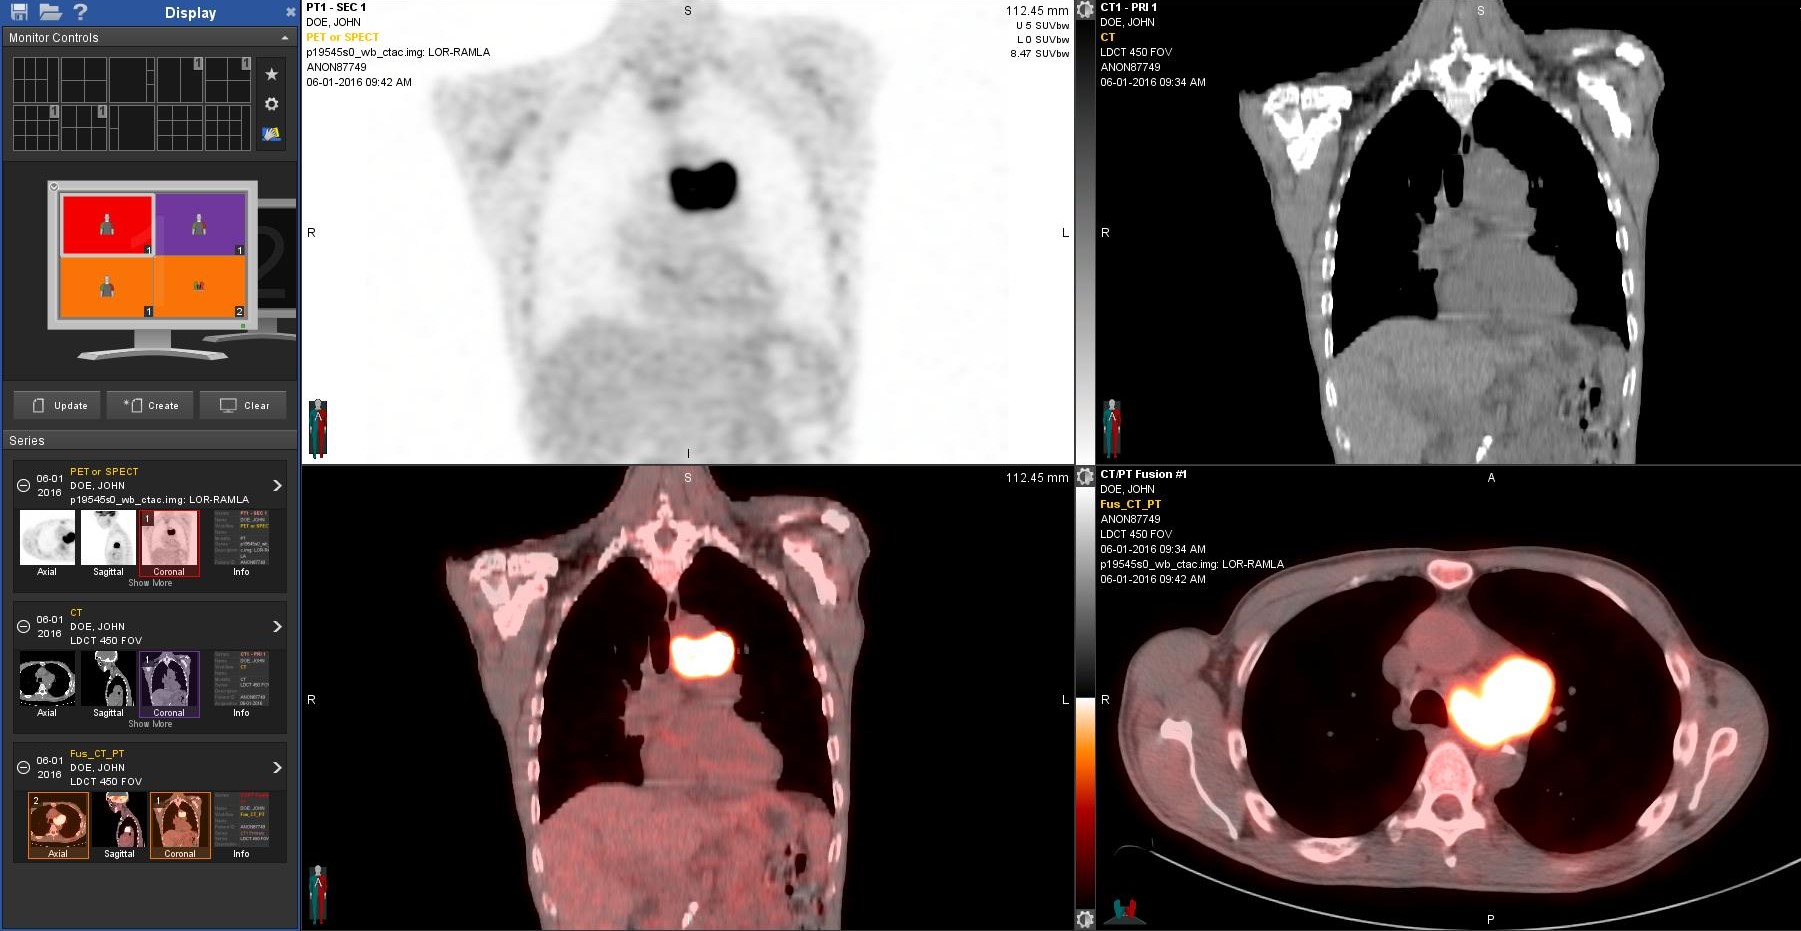

PET is a nuclear medicine technique, which captures images of the human body’s function and reveals information about disease. With PET scan imaging, physicians can collect images of function throughout the entire body, uncovering abnormalities that might otherwise go undetected. No other imaging technique shows the internal metabolism of the body so well. Often times, PET can detect and stage most cancers before they are evident through other tests such as X-ray, MRI, and CT scan. PETalso can give physicians important information about heart viability and neurological disorders, such as Alzheimer’s, seizure disorders and brain tumors.

PET is a reliable, non-invasive way to tell whether or not a tumor is benign or malignant. PET scan imaging evaluates for cancer in a single examination, which allows physicians to stage a cancer and to suggest treatment options earlier, which may spare patients expensive and often painful surgical procedures.

When disease strikes, the metabolism of tissues and cells changes. Using a tracer drug to highlight areas within the body, a PET scan picks up a signal from the organs. If an area in an organ is abnormal, the metabolism will be different than in the surrounding tissues. This data is computer processed and made into images.